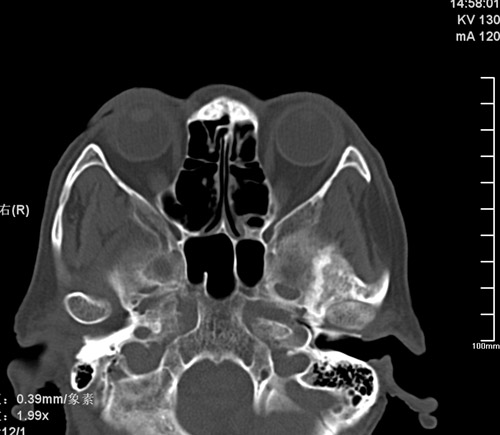

标题: CT17755:女,74 左鼻旁肿胀半年,临床以左上颌窦旁占位行CT [打印本页]

标题: CT17755:女,74 左鼻旁肿胀半年,临床以左上颌窦旁占位行CT

ct考虑鼻前庭囊肿 或鼻翼基底部慢性炎症,左上颌窦少许炎症 请指教

1)考虑左侧鼻前庭囊肿并感染。2)双侧上颌窦炎。

左侧鼻前庭囊肿并感染。双侧上颌窦炎。支持